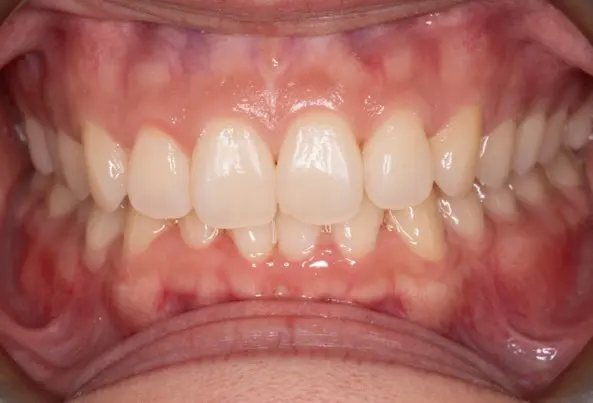

Crowding

Before

After